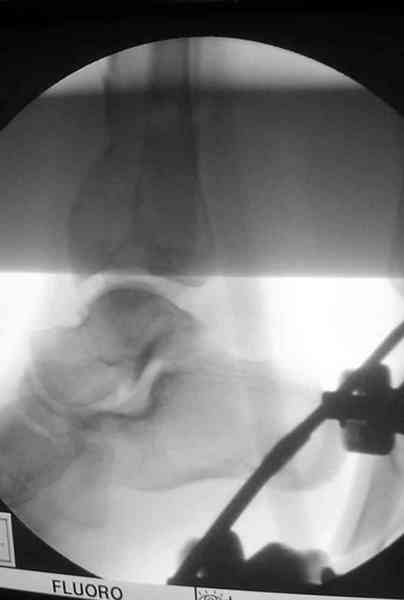

Дополнительные ренгенограммы после дистракции и

обязательная комьютерная томография дают возможности разузнать топографию расположения фрагментов, что немаловажно для планирования хирургического доступа.

По апексу фрагмента ориентируется при планировании

фиксации, также предоперационно определяется

направление фиксирующего материала: шурупа или спицы с упорной площадкой.

Показатель готовности к операции считается когда

“wrinkle probe” на конечности положительная, то есть образования морщинок на коже конечности между двумя пальцами доказывает отсутствия отека, иначе первично невозможно закрыть рану.